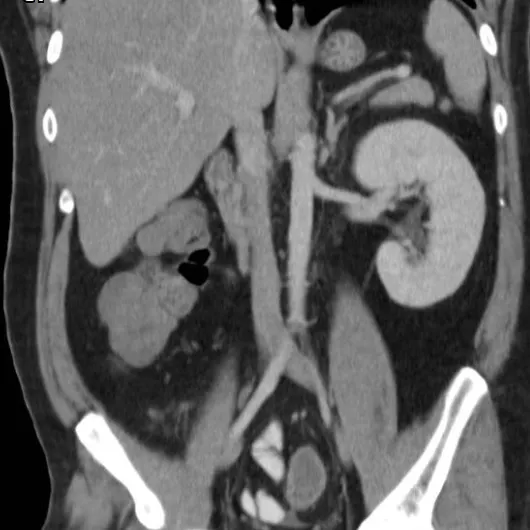

A DRPAD não é contraindicação à DP — e, na prática, muitos pacientes têm resultados comparáveis à hemodiálise. O “porém” está na mecânica: rins/hepatomegalia podem reduzir tolerância a volumes, aumentar risco de hérnias e extravasamentos, e piorar desconforto respiratório. Com técnica adequada (cateter presternal ou lateral, volumes menores, cicladora noturna e decúbito supino), a maioria das barreiras é contornável. Neste post, revisamos quando a DP é ótima, quando exigir cautela e como ajustar a prescrição para segurança e qualidade de vida.